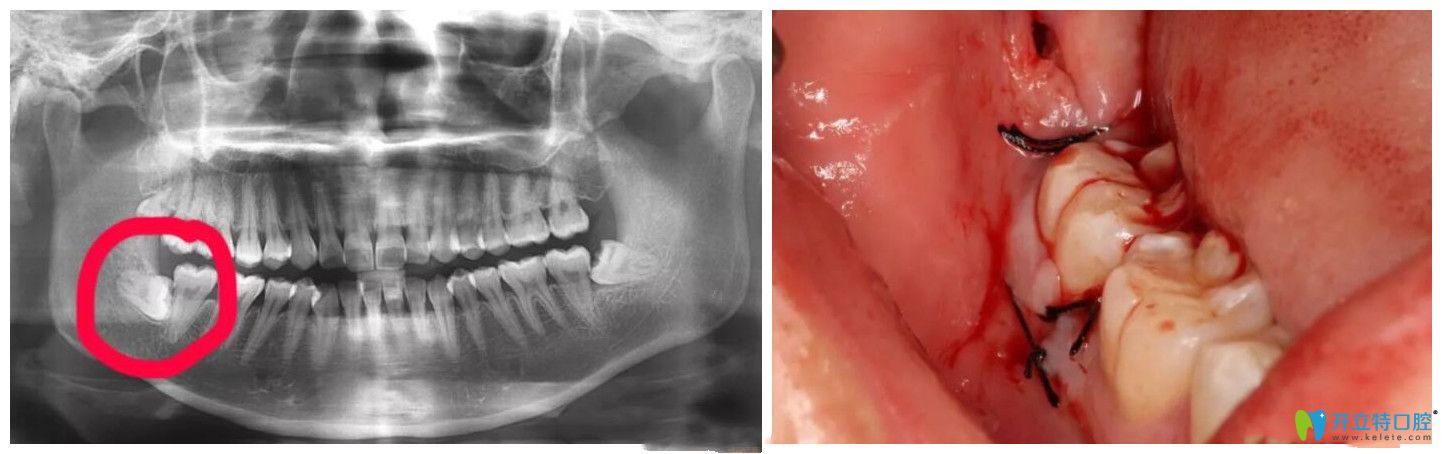

超聲骨刀拔牙真實案例

▲超聲骨刀拔牙真實案例